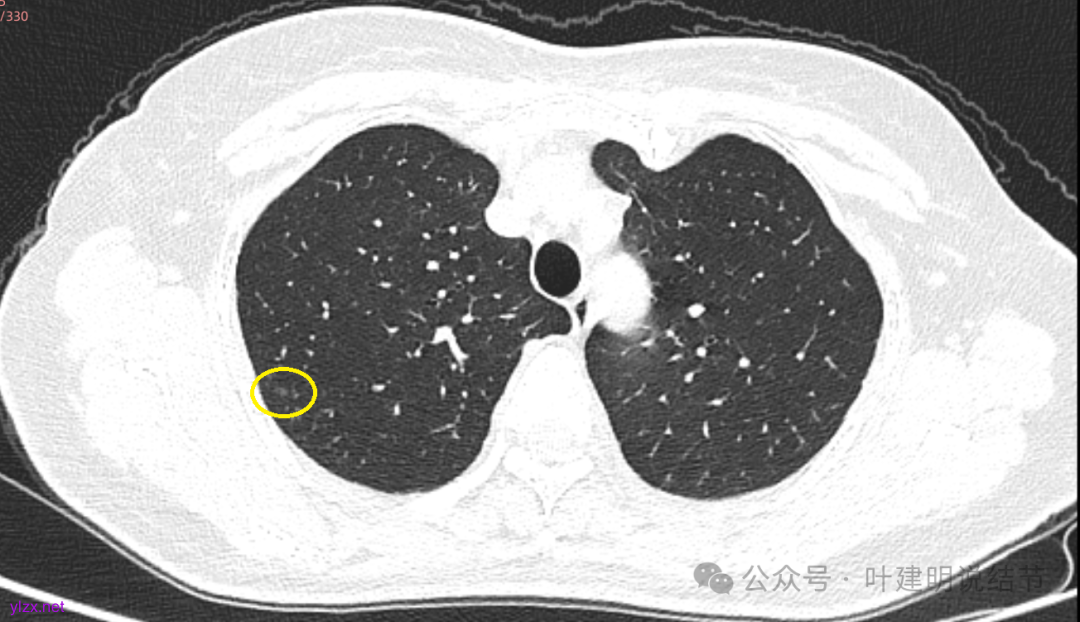

先来看2025年3月的影像:

两肺多发磨玻璃结节,我们主要看最主要的病灶有没有风险或者有没有进展就可以。我是先看2025年的,黄色的微小磨玻璃结节,密度很低,但是轮廓较为清楚,需要考虑肺泡上皮增生或者肺泡间隔增宽,严格意义上应该没有算肺癌,但是以后有可能会发展到不典型增生或者原位癌,当然也可能永远发展不到那个程度,所以目前不需要管;蓝色的到底是肺泡上皮增生还是少许慢性炎不太好确定,因为轮廓稍显模糊,但它又是磨玻璃密度,总归近期是能够随访的;橘色的密度比黄色的略高,有可能会使肺泡上皮增生或者不典型增生,目前也仍可以随访;粉色的是主病灶,位于左肺上叶,混合密度,表面毛糙,由小血管进入,单次看需要考虑微浸润性腺癌可能性较大。然后我们再来看2020年的影像,因为除了粉色的其他的都没有风险,所以不需要一一去找出来,重点关注粉色这处当时是怎样的。我们发现这个病灶5年前就有,也有小血管进入,也有表面毛糙,也是磨玻璃密度,但是当时磨玻璃当中没有实性的成分,是纯磨玻璃伴微小血管进入。对比起来看,这个病灶在5年当中略有进展,原来应该是腺体前驱病变,现在应该是原位癌或者微浸润性腺癌。那么是不是现在就到了一定得马上手术的程度呢?这个仍然可能是不同医生意见会有出入的。假如说从再随访是不是马上会转移来讲,这么小的肿瘤,发展这么慢,而且仍然含有磨玻璃成分,病理考虑与微浸润性腺癌可能性较大,应该仍然不至于说没有随访的空间。但是如果继续随反思想压力比较大,以及即便在随访后续仍然总得要开刀来说,加上病灶位置靠胸膜并不远,简单的单孔胸腔镜楔形切除就能解决问题,将有一定风险的这个病灶切了,同样是可行的。这需要你自己权衡决定。我没有办法100%给十分确切的意见。但是如果从倾向性来讲,由于是多发病灶,加上年纪还轻,风险还不是很大,稍微清一下雨6~9个月复查,有进展病风险再增加再考虑手术。意见供你参考!